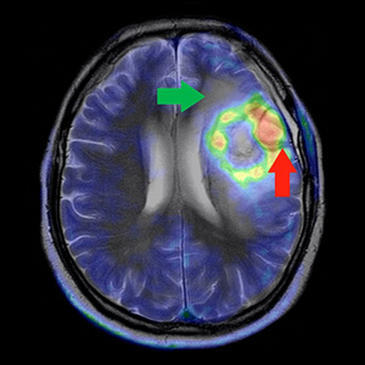

El trabajo se centra en el estudio de imágenes de cerebros obtenidas a través de resonancia magnética. En concreto, han desarrollado un algoritmo para mejorar el proceso de segmentación de imágenes. “Mediante la segmentación —explica Aránzazu Jurío— se separa cada uno de los objetos que forman parte de la imagen. Se analiza cada píxel de manera que todos los que tengan ciertas características en común, se consideran parte del mismo objeto”. En el caso de las imágenes médicas, este proceso es fundamental para la delimitación de tumores donde, si pensamos en zonas como el cerebro, tres milímetros de diferencia pueden marcar la diferencia entre la curación o afectar zonas como el habla o la vista.

Un glioblastoma múltiple, el más común y maligno de los tumores cerebrales. (Fuente: SOM Biotech)